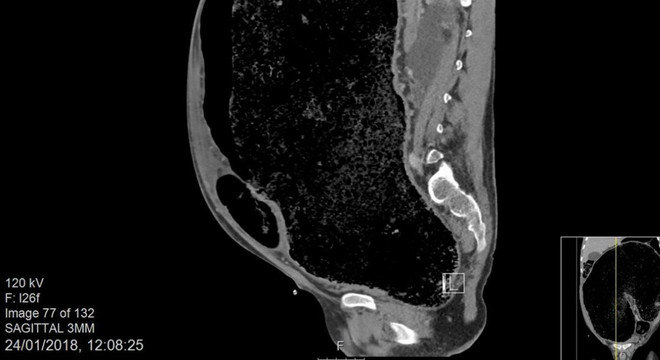

O diâmetro do sigmoide, região em forma de “s” do intestino próxima ao reto que tem cerca de 5 cm, chegou a 18 cm neste paciente.